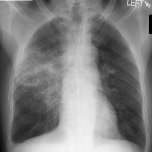

Các virus cúm là tác nhân quan trọng trong các bệnh lý đường hô hấp ở trẻ em. Tổ chức Y tế Thế giới (World Health Organization – WHO) đánh giá có 3-5 triệu ca mắc và 250.000 – 500.000 ca tử vong do virút cúm mỗi năm trên thế giới. Tỷ lệ tử vong ở trẻ nhiễm virút cúm tuy thấp nhưng tỷ lệ trẻ có nguy cơ cao hoặc phải nhập viện có liên quan virút cúm vẫn khá cao, đặc biệt đối với trẻ < 2 tuổi. Biểu hiện bệnh thường rất thay đổi, từ không có triệu chứng lâm sàng đến các trường hợp bệnh có biến chứng đa cơ quan. Viêm phổi là một trong các biểu hiện rất thường gặp, mặc dù chưa có nhiều nghiên cứu về các tổn thương và biểu hiện lâm sàng của bệnh.

- Các biểu hiện lâm sàng thường gặp gồm sốt và ho (100%), nghe phổi có ran nổ (90%);